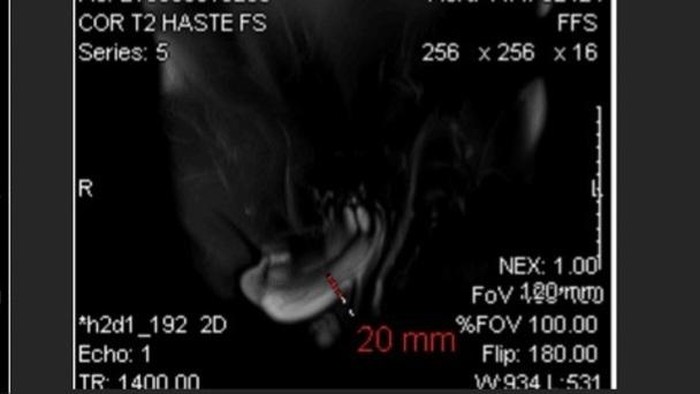

Dokter lalu melakukan pemeriksaan USG dan menemukan caca hiposekolik pada tunika albuginea korpus kavernosum kiri bekuruan kurang lebih 1 cm. Karena hasilnya kurang meyakinkan, dokter lanjut melakukan pemeriksaan magnetik resonance imaging (MRI).

Hasilnya, dokter menemukan robekan sepanjang 2 cm pada tunika albuginea penis. Dokter juga menemukan hematoma atau perdarahan yang terperangkap oleh fascia buck, lapisan jaringan ikat yang menyelubungi struktur utama penis.